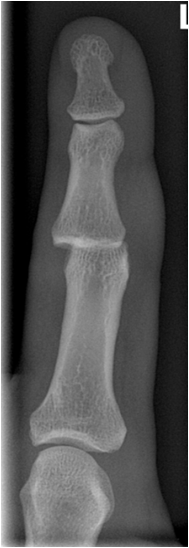

Fig. 11. Growth plate fracture with involvement of metaphysis and epiphyis (Salter-Harris type IV.